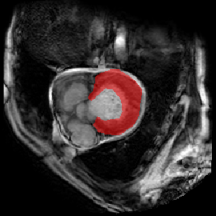

Figure 5 provides a visual representation of our model’s segmentation, indicating its superior accuracy, particularly in the right ventricle (RV) organ. While other methods display complete segmentation, our segmentation aligns more closely with the real mask.